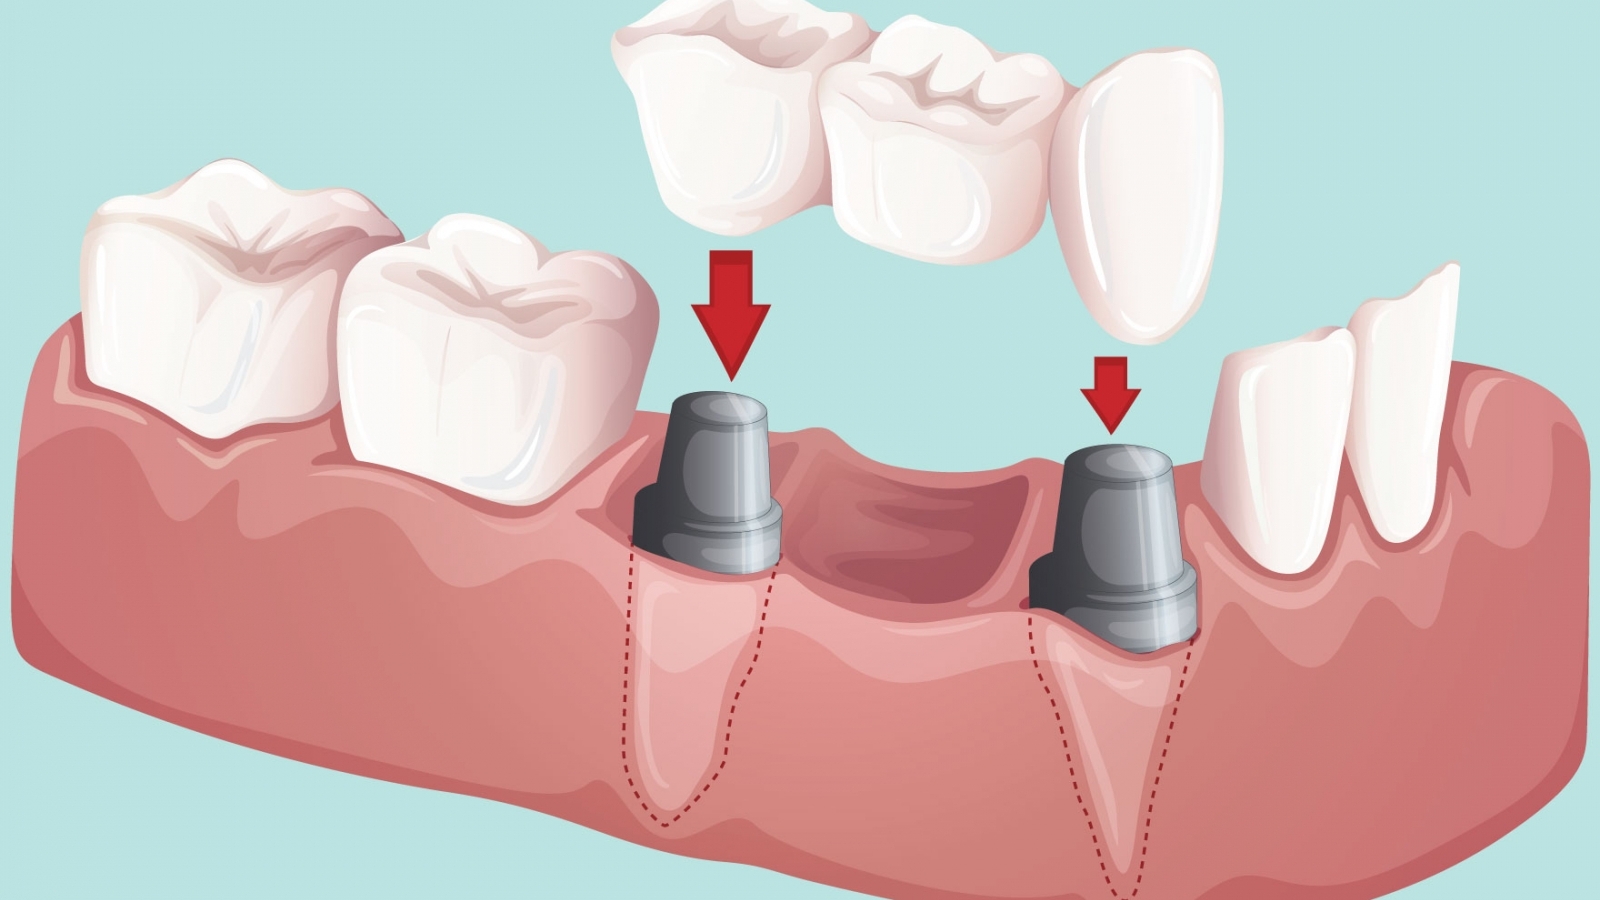

Cầu răng

Hiện nay trong lĩnh vực Nha Khoa, 2 phương pháp để phục hồi răng đã…